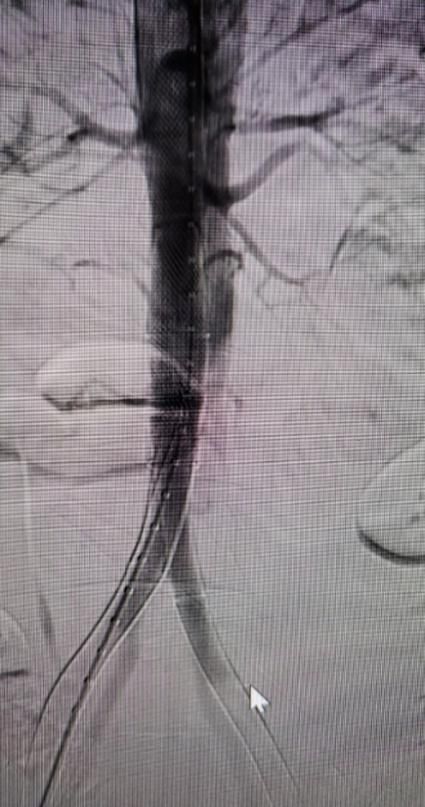

在麻醉科何沛霖教授的配合下,此次手术过程进展顺利,植入时间仅40分钟,支架近端锚定象鼻支架内部,远端至双侧髂动脉,覆盖残余夹层全长,成功封堵所有破口。

图1 术后造影显示真腔明显扩张

术前造影

支架植入后造影